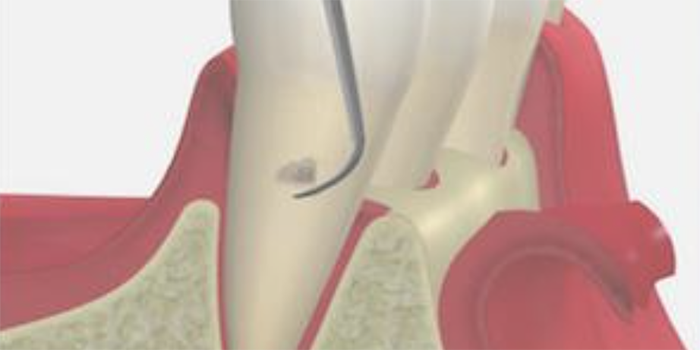

3. SRP

(スケーリング・ルートプレーニング)

専用の器具を使って、歯ぐきの中にある汚れを除去して、歯の根っこ部分の表面を汚れの付着が起こりにくい状態に仕上げる処置です。

主に、歯ぐきの中にまで歯石が入り込んでいる中等度以上の患者さまに対して行います。痛みが強い場合は、麻酔をして行うこともあります。

歯と歯茎の間の汚れをかき出すイメージイラスト

4. 歯周ポケット掻爬術

歯ぐきの内側の炎症をおこしている組織を取り除く処置です。

麻酔の効いている状態で行うため、治療中の痛みはほとんどありません。

内側からの炎症改善を目的としており、清潔になった歯の根に歯ぐきが付着し、汚れが溜まりにくい環境を作ることができます。

歯周ポケット掻爬術のイメージイラスト